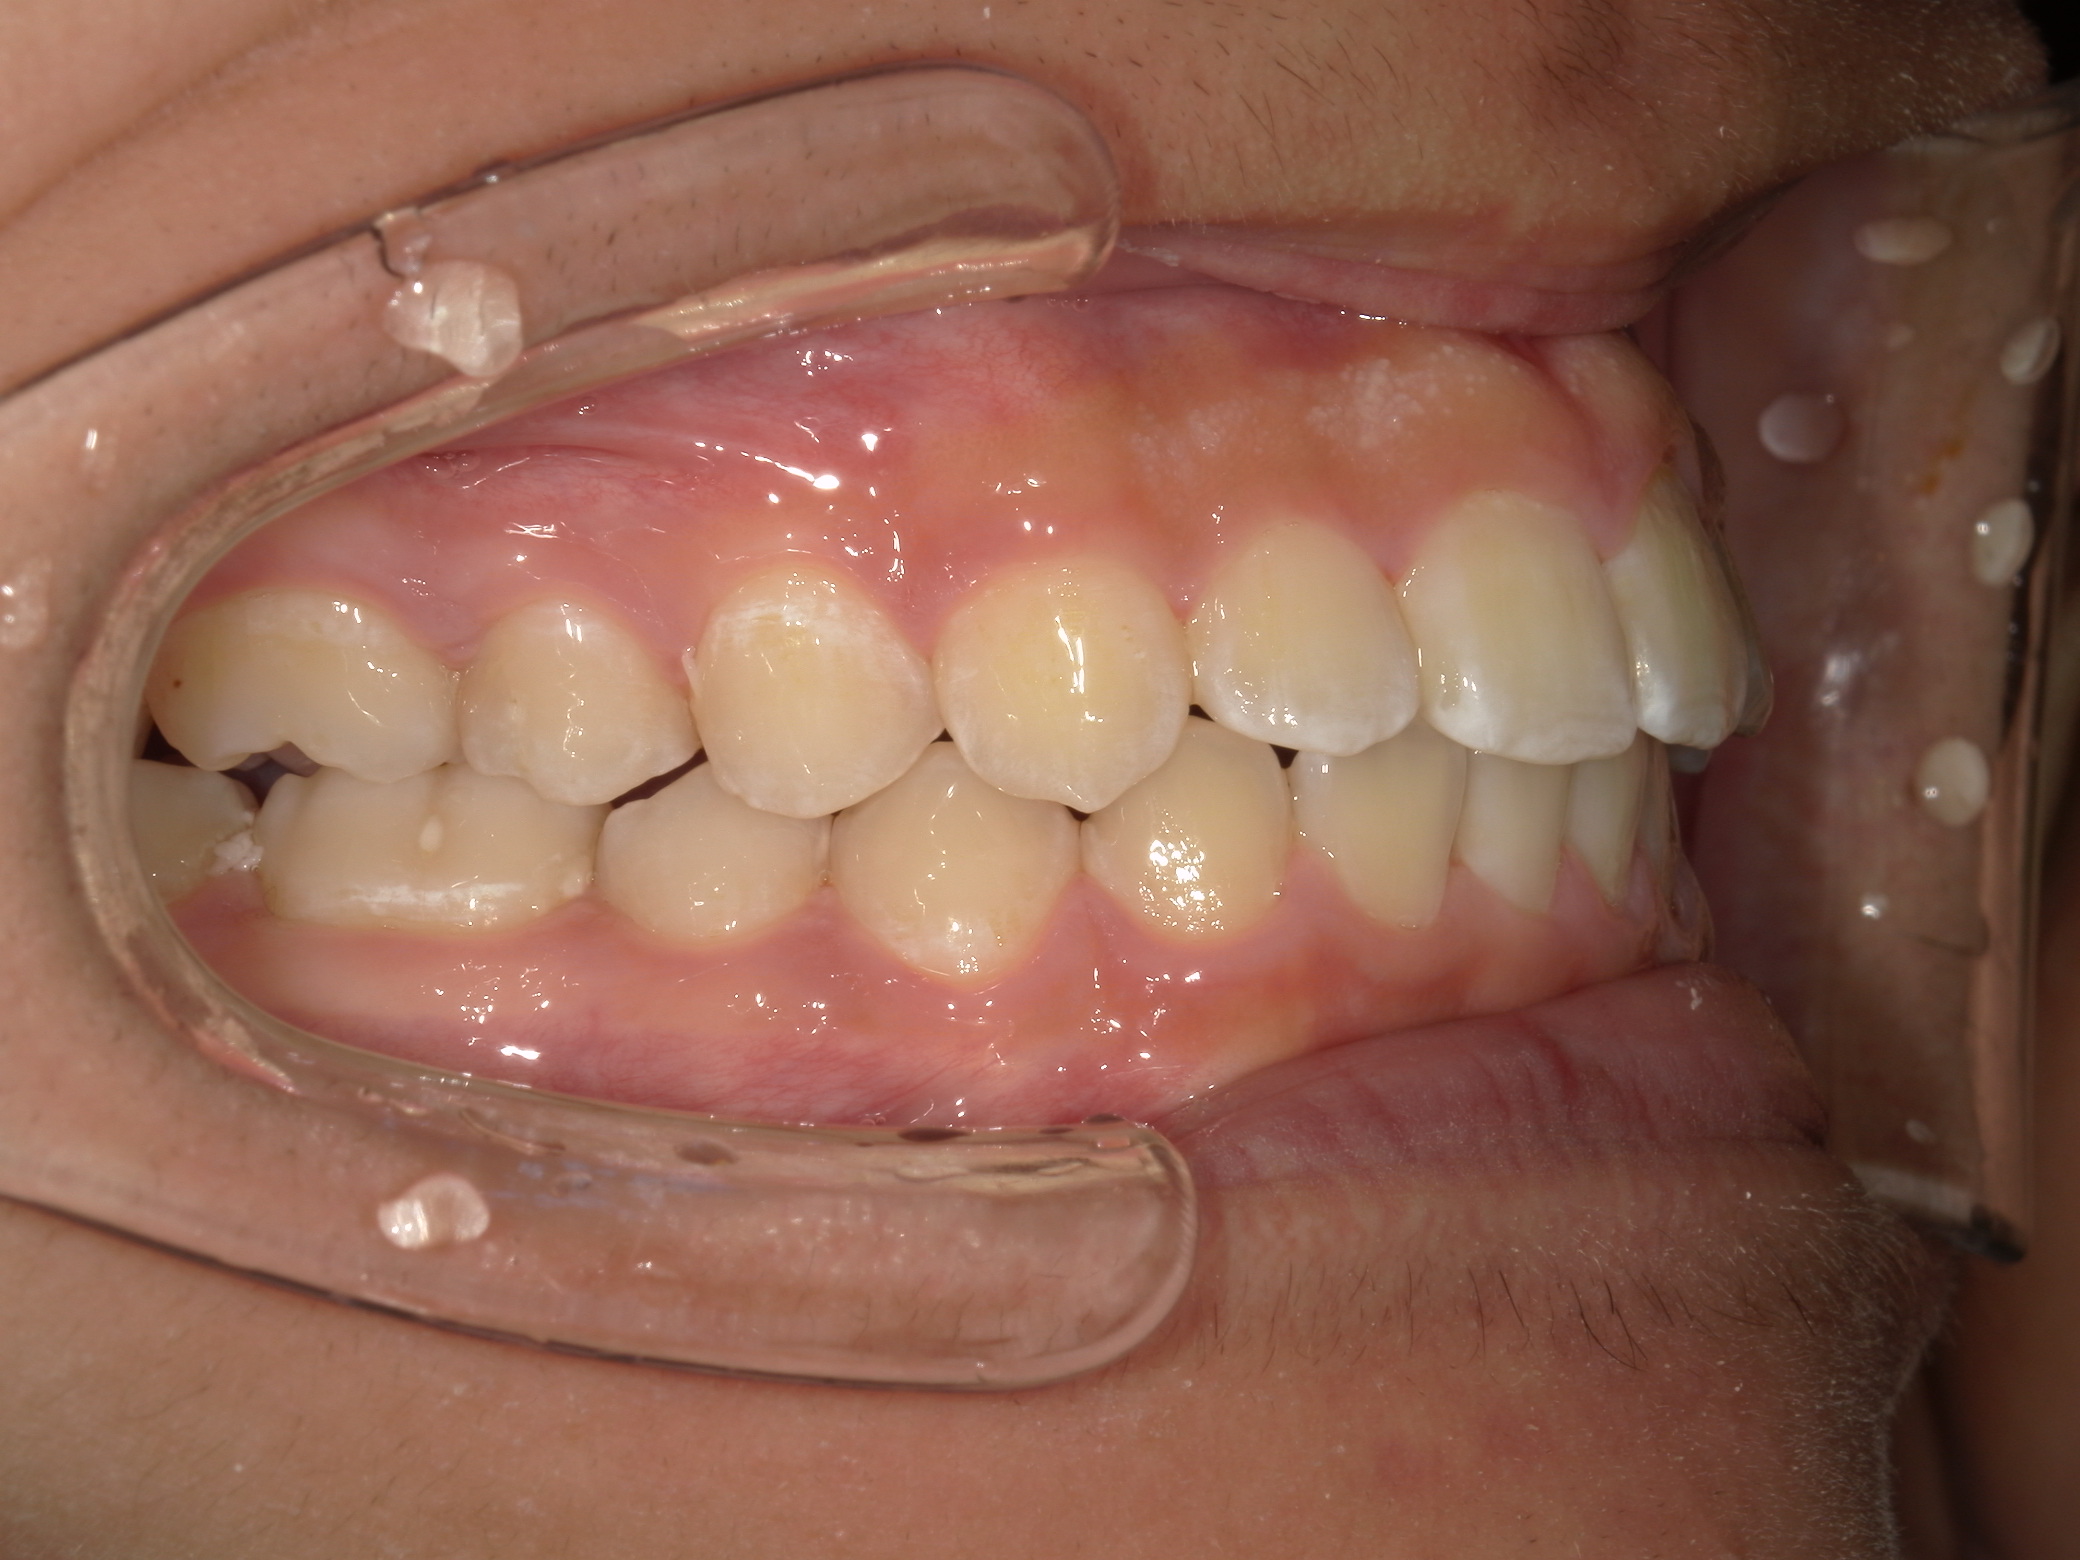

非抜歯アンカー矯正の初診時|奈良の矯正歯科

初診時